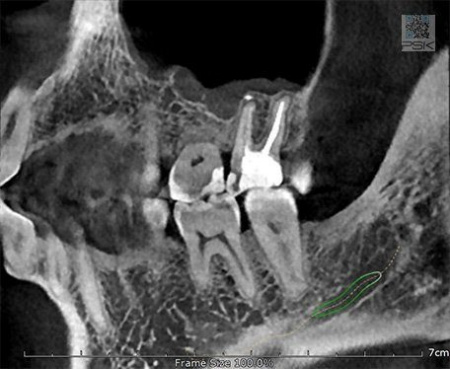

70 мкм в Эндодонтическом режиме 3,5×4 см

Высокотехнологичный детектор с самым высоким разрешением в классе – 70 мкм. Позволяет различить даже самые мелкие анатомические образования и облегчит постановку диагноза в сложных случаях. А вместе с применением алгоритма SMARF инородные тела из металла не испортят качество снимков.

Умная Функция Уменьшения Артефактов от Металла (Smart Metal Artifact Reduction Function) – позволяет минимизировать артефакты от вторичного излучения металлов и получить необходимую диагностическую информацию для постановки корректного диагноза, а также планирования и контроля проведенного лечения.